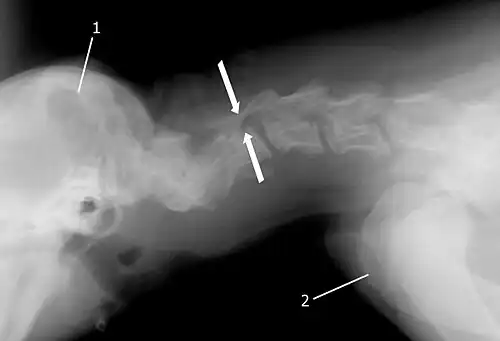

Die Röntgendiagnostik ist für die Diagnosestellung unverzichtbar. Da der Patient hier optimal gelagert werden muss, ist sie bei Hunden praktisch nur unter einer Kurznarkose sinnvoll durchführbar.[6] Aufnahmen werden im seitlichen und ventrodorsalen (von der Halsunterseite her) Strahlengang in Normalstellung sowie bei gebeugtem Hals durchgeführt.

Röntgenaufnahmen ohne Kontrastmittel („Nativaufnahmen“) sind meist nur von begrenztem Aussagewert. Allenfalls das „vertebral tipping“, Stufenbildungen oder Keilwirbel lassen sich sicher diagnostizieren. Lewis[7] schlug vor, die Größe zwischen Ein- und Ausgang des Wirbelkanals eines Wirbels zu vergleichen. Eine Größendifferenz von mehr als 3 mm spricht bei einem Dobermann für das Vorliegen einer zervikalen Malformation.

Da Nativaufnahmen nur eine geringe diagnostische Sicherheit haben, müssen Röntgenaufnahmen mit Kontrastmittel (Myelografie) folgen, die nur unter Narkose angefertigt werden können. Nach Gabe des Kontrastmittels werden Normal- und Stressaufnahmen (stark gebeugter und überstreckter Hals, Längszug) durchgeführt. Mit der Myelografie lassen sich Verengungen des Wirbelkanals relativ sicher nachweisen.